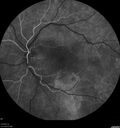

Bilateral Acute Central Serous Chorioretinopathy - Evidence of old disease OS311 views64 year old man noticed in the right eye that is a black spot 4 days ago. Also vertical lines in his kitchen were a little wavy. He is not on any steroid medications. He has vertigo.

VA OD: Dcc20/25-2 NccJ1+-3

VA OS: Dcc20/32-1 PHNI NccJ5-1

IOP: TP: OD:12 OS:15